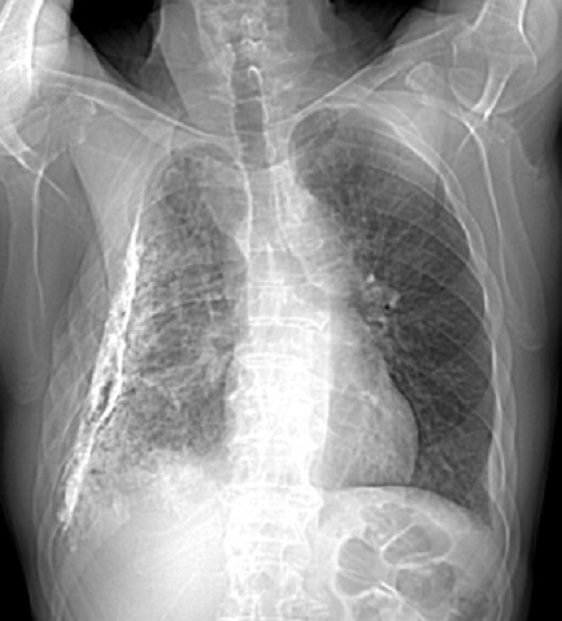

Image

radiolologique cliche de face PA d'une epaissisement

pleural diffuse du poumon droit par consequence de

tuberculose du poumon droit . Aspect radiologique

est opacite en plaque de tres densite s'étend et

recouvre tout le poumon droit , Poumon droit en

fibrose restrictive |